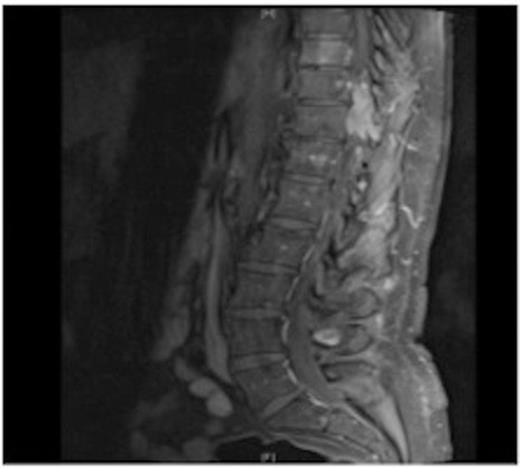

MRI showing the T10-11 extra-dural tumour with erosion of the T12 pedicle

On review of the original thoracic CT scan, which was performed 2 months prior to the MRI, the tumour was distinguishable but, as the spine is such a rare location for carcinoid metastasis, it was initially unreported.